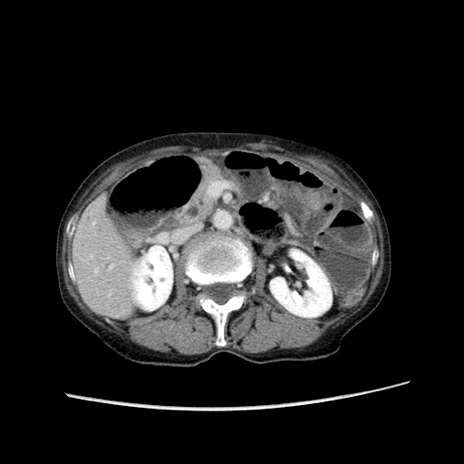

症例25(横断像)

【症例】80歳代女性

【主訴】胸のつかえ感

【現病歴】約9時間前に食後から胸のつかえた感じあり、嘔吐あり、来院。

【既往歴】胃癌(全摘)、胆摘、虫垂炎

【身体所見】心窩部に圧痛あり、反跳痛なし。

【データ】WBC 5700、CRP 0.05